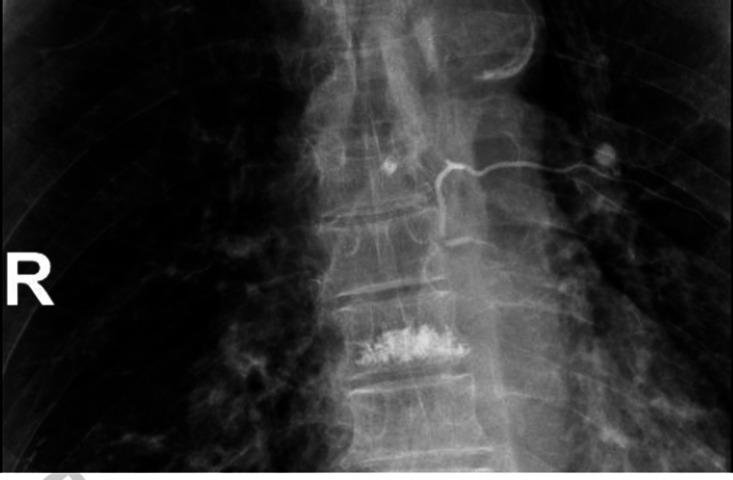

We present a case of an 81-year-old man with gallbladder gangrene after percutaneous vertebroplasty (PV) that was successfully treated via laparoscopic cholecystectomy (LC). The patient underwent multilevel, thoracic PV for painful osteoporotic compression fractures. PV performed at the T6 level was complicated by severe abdominal pain owing to direct embolization of the right T6 segmental artery with penetration of bone cement into the radicular artery beneath the pedicle. Cement leakage, especially arterial embolization of cement into the general circulation, is a known potential complication following PV. Serious complications related to PV augmentation procedures, such as vertebroplasty and kyphoplasty, are rare and most often result from local cement leakage or venous embolization. Combined with this case report, we reviewed the literature regarding the unusual occurrence of direct arterial cement embolization during PV and analyzed the causes to alert clinicians to this potentially rare vascular complication.

我们报告了一例 81 岁男性患者,在经皮椎体成形术(PV)后发生胆囊坏疽,通过腹腔镜胆囊切除术(LC)成功治疗。患者因多节段胸段 PV 治疗骨质疏松性压缩性骨折而出现疼痛。T6 水平的 PV 出现严重腹痛,原因是骨水泥直接栓塞右 T6 节段动脉,并穿透椎弓根下的神经根动脉。骨水泥渗漏,特别是骨水泥动脉栓塞进入体循环,是 PV 后已知的潜在并发症。与 PV 增强术相关的严重并发症,如椎体成形术和后凸成形术,较为罕见,且通常由局部骨水泥渗漏或静脉栓塞引起。结合本病例报告,我们复习了关于 PV 期间直接动脉骨水泥栓塞罕见发生的文献,并分析了其原因,以提醒临床医生注意这种潜在的罕见血管并发症。